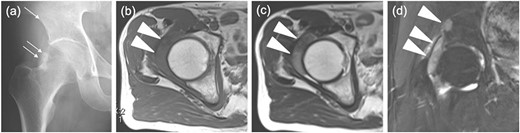

The radiographs showed calcification around the right femoral neck (Fig. 1a). The magnetic resonance image (MRI) showed an intra-articular lesion, which revealed that the mass was 40 ×10 × 42 mm and located at the anterolateral side of the femoral neck. The mass was isointense, slightly hyperintense and hyperintense compared with skeletal muscle on T1- and T2-weighted and T2 fat-saturated images, respectively (Fig. 1b–d). In addition, MRI showed a pelvic bone lesion, as well (Fig. 1d). At this point, we did not speculate the possibility of malignant tumor, then planned arthroscopic treatment for biopsy and tumor excision. A simple excision was performed via arthroscopic surgery, but the pelvic lesion was not excised. The arthroscopic image demonstrated a hyperemic soft tissue mass in the hip joint (Fig. 2). Removal of massive lesion and intra-articular debridement by shaver and radio frequency device was performed as much as possible.

Images before the arthroscopic surgery. (a) A radiograph showed the calcification at the anterolateral side of the right femoral neck (two arrows) and a radiolucent shadow of the pelvic bone (an arrow). Axial (b) T1-, (c) T2-weighted image (T1WI, T2WI) and (d) coronal T2 fat-saturated (T2 fs) image revealed the intra-articular lesion in the right hip joint (two headless arrows). The mass was 40mm×10mm×42mm and isointense, heterogenous and hyperintense to skeletal muscle on T1WI and T2WIand T2 fs images respectively. T2WI showed triple signal intensity sign9. In addition, the coronal T2 fs image showed a pelvic bone lesion (a headless arrow).